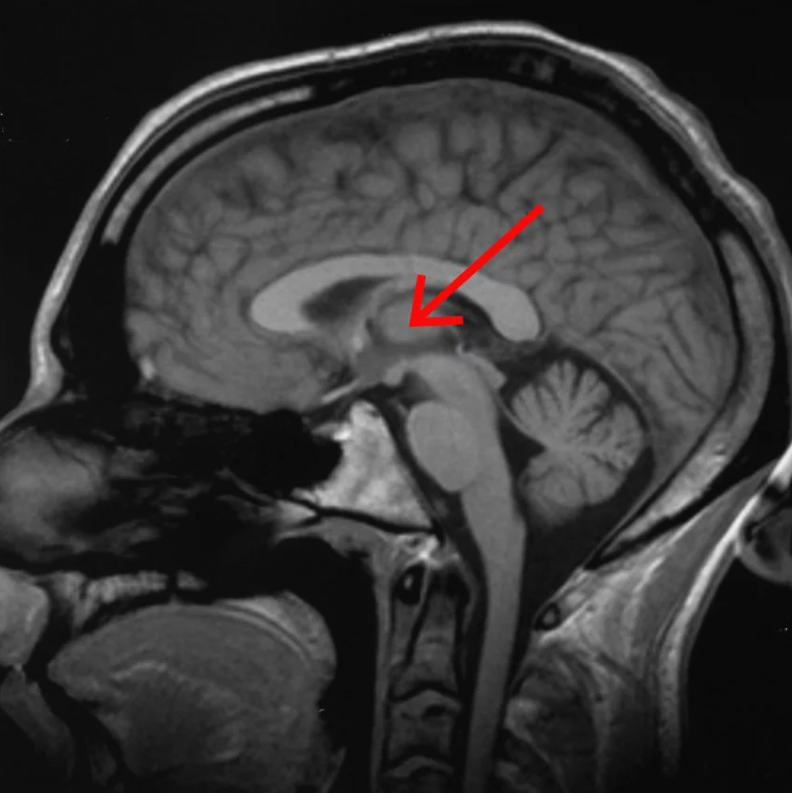

Researchers find a “consciousness switch” deep in the brain

“The researchers hope this discovery might be able to help people with “disorders of consciousness” – for example, it might be possible to bring people out of comas with consciousness-starting devices, or give narcolepsy sufferers the ability to self-stimulate when they’re falling asleep at an inopportune time.”